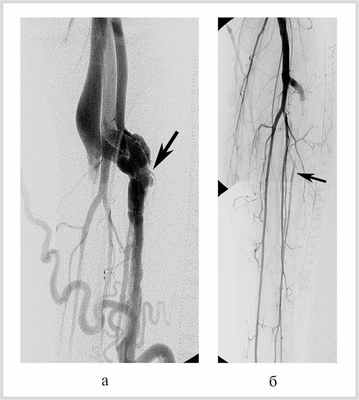

Эндопротезирование с перекрытием устья позвоночной артерии, несущей аневризму, выполнено в одном наблюдении при ее окклюзии дистальнее свища (рис. 3).

Рис. 3. Травматический артериовенозный свищ левой подключичной артерии со сбросом в подключичную вену. Эндопротезирование левой подключичной артерии.

Эмболизирующие спирали были использованы в 5 наблюдениях. Эмболизация артерии-источника проксимальнее устья аневризмы была выполнена дважды — при вмешательствах на наружной височной артерии и печеночных артериях; окклюзия полости аневризмы — при свище подключичной артерии в первом сегменте; эмболизация артерии-источника дистальнее и проксимальнее шейки аневризмы — при операции на селезеночной артерии; эмболизация артерии-источника проксимальнее устья аневризмы и ее полости — с целью разобщения артериовенозного соустья глубокой артерии бедра.

Окклюзия спиралями применена у больного с артериовенозной аневризмой подключичной артерии из-за близости ее шейки к устью правой позвоночной артерии. Установка стент-графта могла бы, с одной стороны, привести к ее окклюзии с крайне высоким риском ишемического повреждения головного мозга из-за особенностей внутричерепных артериальных анастомозов, с другой стороны, если бы мы стремились к обязательному сохранению кровотока по позвоночной артерии, — к неполному перекрытию шейки аневризмы [9]. Направление хода артериовенозного свища потребовало применения плечевого артериального доступа. Эмболизация была начата с имплантации двух эмболизирующих спиралей несколько большего диаметра, чем поперечный размер аневризмы, которые, благодаря этому, были уложены в ее полости в виде восьмерок, как трехмерный конгломерат. Затем, для более плотного заполнения полости аневризмы, были установлены две спирали меньшего диаметра, благодаря чему удалось избежать применения дополнительных эмболизирующих агентов [9]. Это позволило ликвидировать артериовенозный сброс, сохранить антеградный кровоток по правой подключичной артерии.